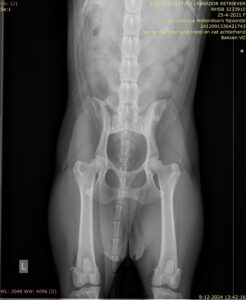

HD (Heupdysplasie)

Heupdysplasie (HD) is een ontwikkelingsstoornis van de heupgewrichten. Het kan erfelijk zijn, maar omgevingsfactoren spelen ook een rol bij de ontwikkeling. Een hond kan veel last hebben van HD, maar dat hoeft niet. Aan de buitenkant kun je niet zien of een hond HD heeft, dus als je hond goed kan lopen, hoeft dat nog niet te zeggen dat zijn heupen perfect zijn. Om echt te kunnen zien of je hond HD heeft, zijn (digitale) röntgenfoto’s van zijn heupen nodig.

Er zijn verschillende FCI-einduitslagen mogelijk:

- HD A (=negatief):

je hond is op basis van de röntgenfoto vrij van HD; dit betekent niet dat je hond geen “drager” van de afwijking kan zijn. - HD B (=overgangsvorm):

op de foto’s zijn kleine veranderingen zichtbaar die het gevolg zijn van heupdysplasie. - HD C (=licht positief) of HD D (=positief):

je hond laat duidelijke veranderingen zien die passen in het ziektebeeld van HD. - HD E (=positief in optima forma):

de heupgewrichten zijn ernstig misvormd.

Houd er rekening mee dat een HD A uitslag niet betekent dat je hond nooit last zal krijgen van HD. Omgekeerd betekenen duidelijke misvormingen ook niet dat de hond er beslist last van zal krijgen. Het is wel verstandig om er op te letten dat je (de heupgewrichten van) je hond niet te zwaar belast. In geval van twijfel kun je dit met je dierenarts bespreken.